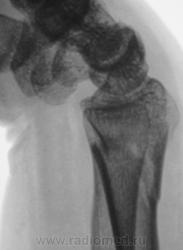

Травма.   Пациент направлен на рентгенографию лучезапястного сустава.

Вывих трапеции и гороховидной костей, ну и перелом "луча" в т.м., куда же без него.